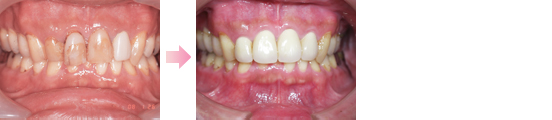

症例1

症例1 ・・・禁煙後レーザー治療を行いました。後にホワイトニングを含めた審美治療を行います。